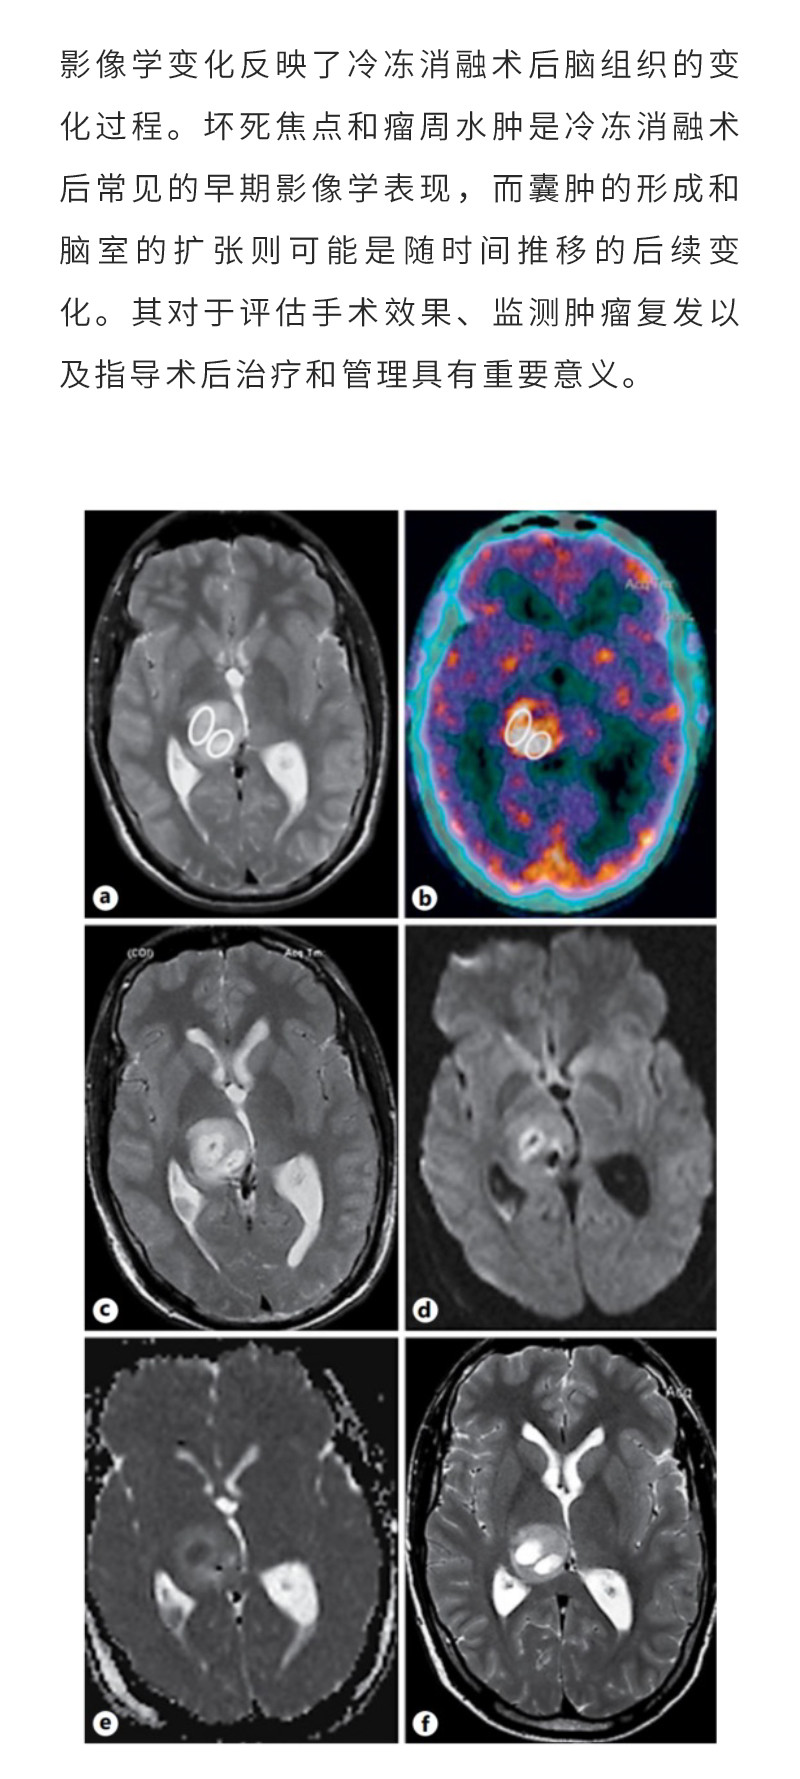

冷凍消融腦膠質(zhì)瘤——【海杰亞科研資訊】第283期